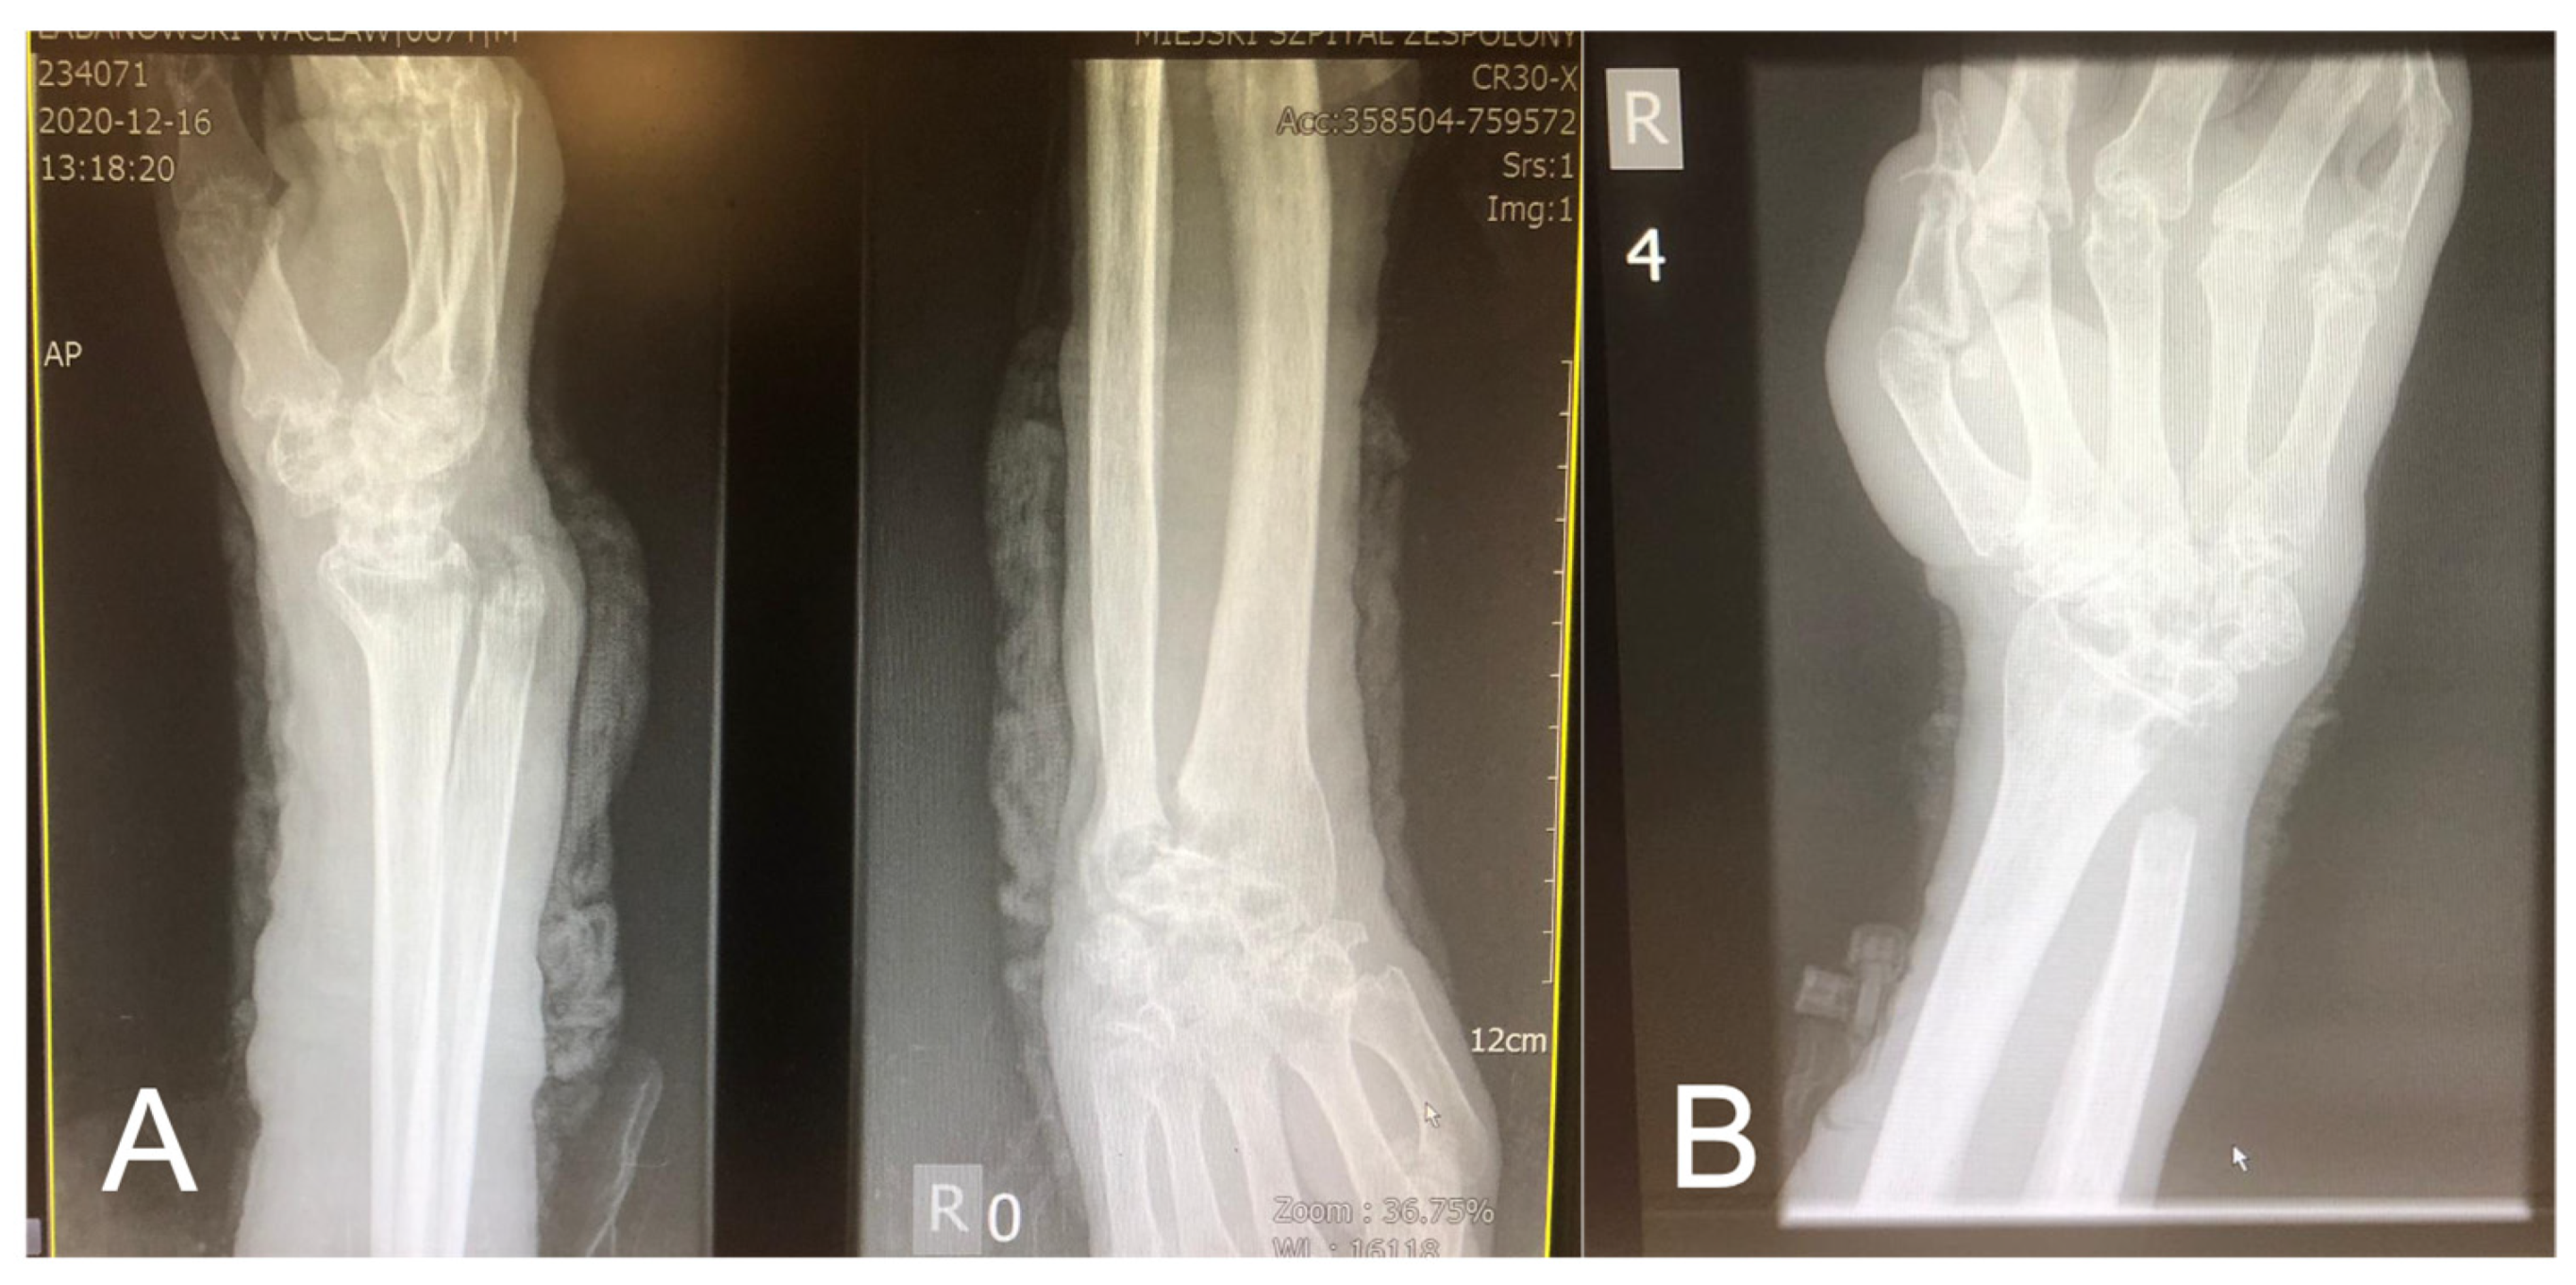

During the hospitalization, the patient was transferred to the Orthopedic Department for several days. He underwent a resection of the right distal ulnar epiphysis, removal of the necrotic tissue from the forearm, and wrist abscess fistula, with the coverage of the skin loss with Optilene mesh. The procedure was performed due to purulent inflammatory fistula of 1/3 of the distal forearm and right wrist with trophic skin loss, liquefactive soft tissue necrosis, and the dislocation of the ulnar head in the distal radioulnar joint (Figure 5A,B).

Figure 5. (A) X-ray of the right upper limb—subluxation of the wrist, contour deformity with a draining fistula of the head of the ulna; (B) X-ray after the resection of 1/3 of the distal right ulna.